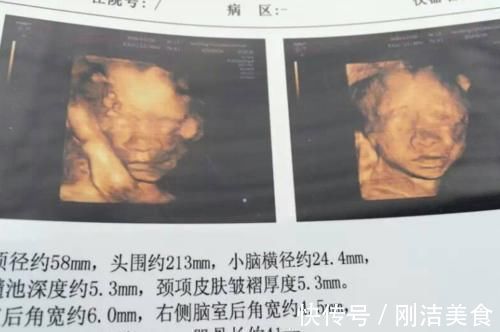

准妈妈在孕期要经历很多检查,其中四维不仅是为了看看胎宝的发育情况,还能一睹胎宝的“真面目”。

在医院检查一番后拿到结果,得知胎宝的身体很健康,而且胎位正,想要顺产的话还是有希望的。于是夫妻俩问过医生注意事项后,就高高兴兴地回家了。回到家后,婷萱拿着检查结果反复研究后发现,她肚子里的这个小家伙,颜值并不高。

胎宝鼻子和嘴巴都大大的,与自己精致的五官相差很多,于是婷萱和丈夫说:“宝宝这么丑一点都不像我,一定是像你”。

四维照可以说是小宝宝的第一张照片,但隔着一层妈妈肚皮,还原度不是很高,只能作为颜值的参考,之所以胎宝看起来很丑是由于以下3个原因。

给胎宝拍四维照,不仅要透过准妈妈的肚皮,还要透过胎宝周围的羊水。这就好像我们在拿手机拍照时,前面有一个水杯挡着,这时拍出来的照片,肯定和宝宝真实的颜值有差别。

所以说胎宝不一定有照片上那么丑,准爸妈要有信心,胎宝出生后还是可以变美的。